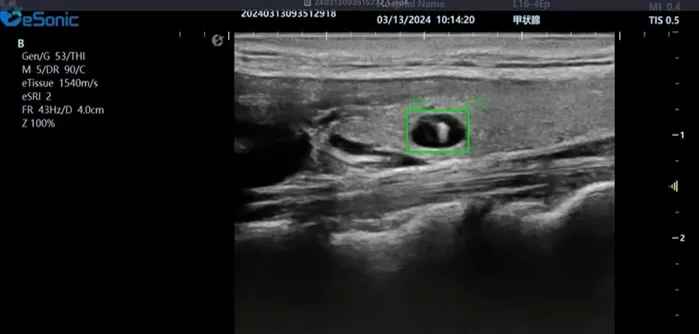

新航娱乐医疗(ESI)表示,其最新的人工智能功能可以帮助到医疗机构的工作效率,功能包括,实时、动态、快速自动识别病灶,良恶性病灶概率预测,甲状腺结节和乳腺的二维灰阶动态自动实时检测需求,提供多个结节动态检测轮廓框。实时获取多幅具备临床特征(大小、属性等)的结节切面,同时提供当前切面所示结节的结节大小、属性特征、TI-RADS 分级。

对于甲状腺结节相关的自动检测功能,甲状腺结节病灶检出率≥95%,良恶性分类灵敏度≥90%、良恶性分类特异度≥85%。